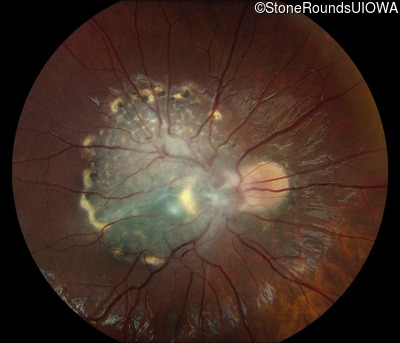

This 9 year old male was noted to have some crossing of his eyes at 2 months of age and the eye exam which followed identified a retinal lesion in the right eye. When he was six years old an epiretinal membrane was noted in his left eye. Two years later it was decided that it was a thin hamartoma in that eye as well. He underwent neuroimaging at age 7 which identified bilateral acoustic neuromas.

| Age at visit: 8 years |

| Age at visit: 10 years |

| Age at visit: 11 years |

| Age at visit: 14 years |